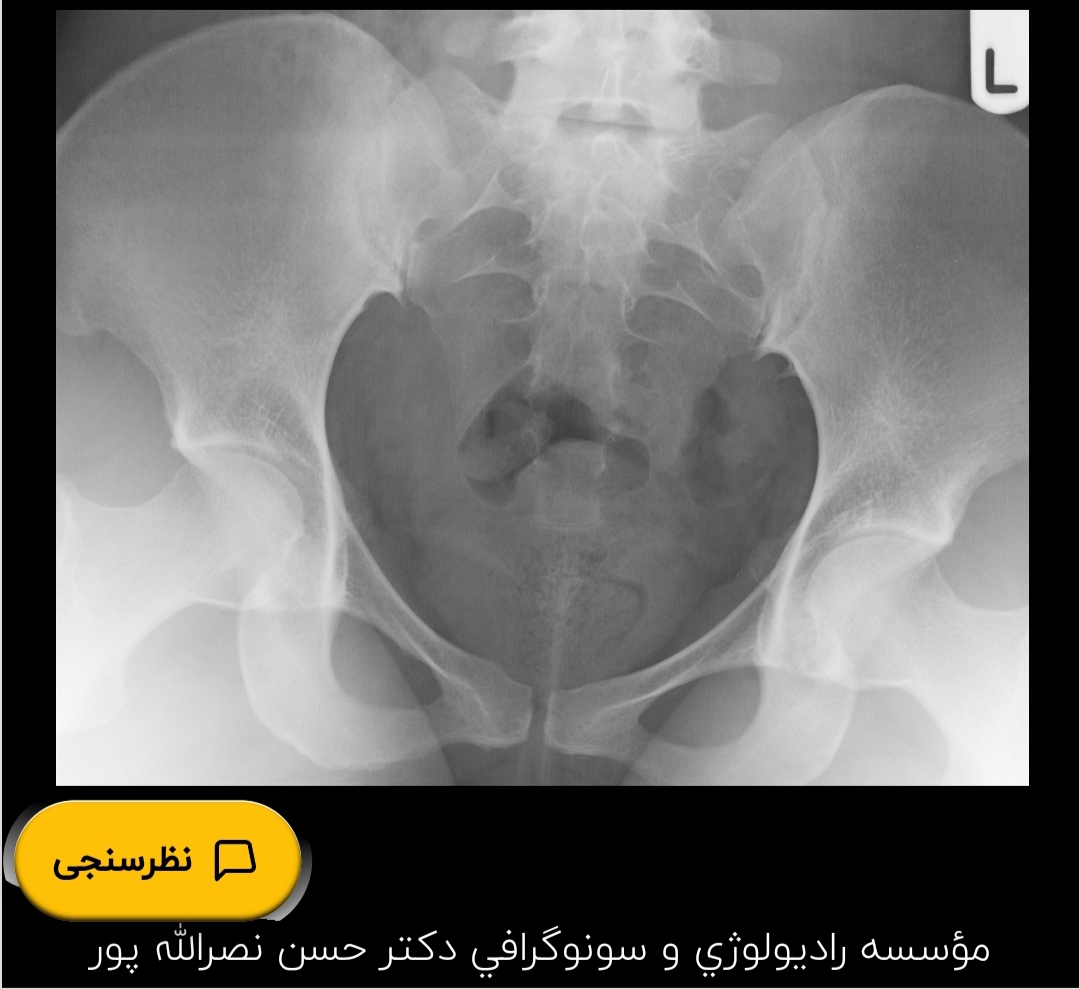

سلام خانم دکتر عزیز و اومایی های گل.من پنج ماهه اقدام به بارداری کردم و باردار نشدم الان عکس رنگی رحم انجام دادم و بهم گفتن ی لوله بیشتر ندارم آیا امکان بارداری طبیعی با ی لوله هست یا نه

تفسیر عکس رنگی رحم

من اصلا ی لوله ندارم کلا

خانم دکتر آیا با این ی لوله و رحم تک شاخ بارداری طبیعی صورت میگیره یا باید از آی وی اف کمک بگیریم؟